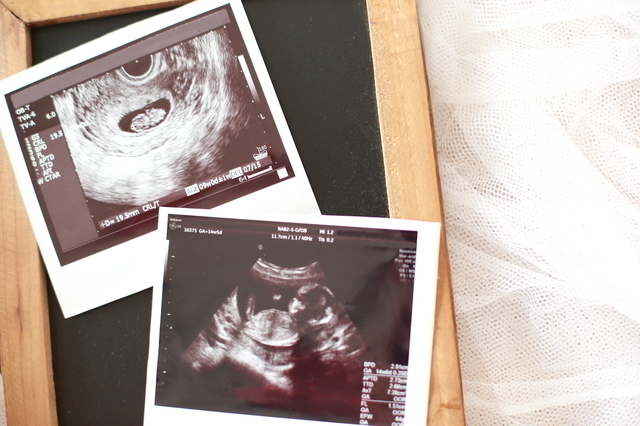

妊娠12週のおなかの状態

妊娠12週の赤ちゃんの状態

いかがでしたでしょうか?妊娠12週になると、赤ちゃんも人間らしい形になってくるので健診でのエコーチェックもママやパパの楽しみになってきますね。